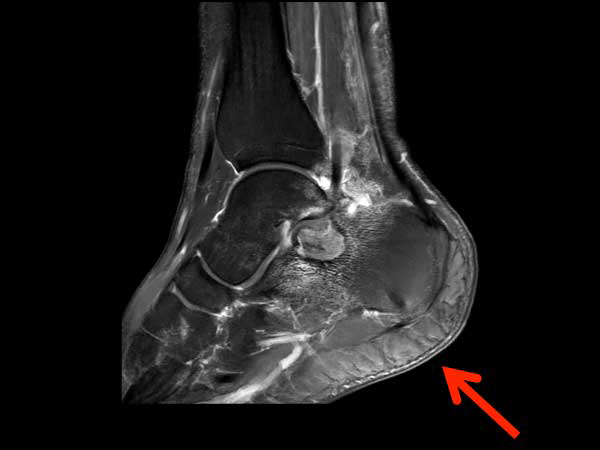

Sagittal T1w mDIXON (post gado)